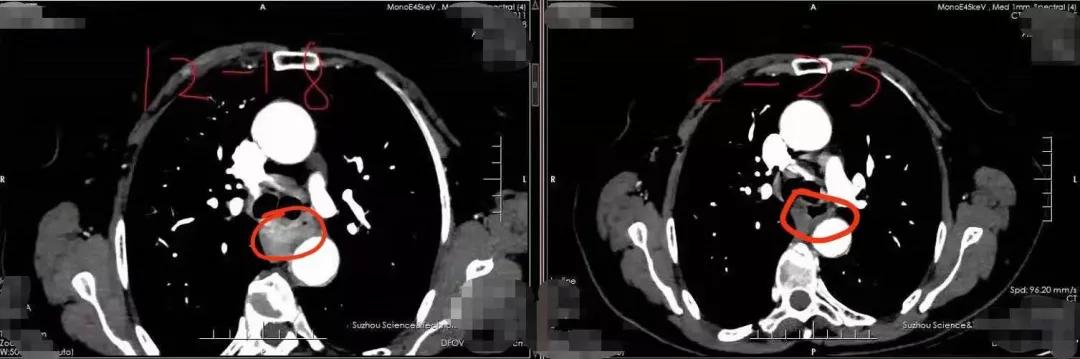

因为瘤体比较大

有5.3*1.5厘米

治疗后肿瘤明显缩小

变成3.2*0.8CM